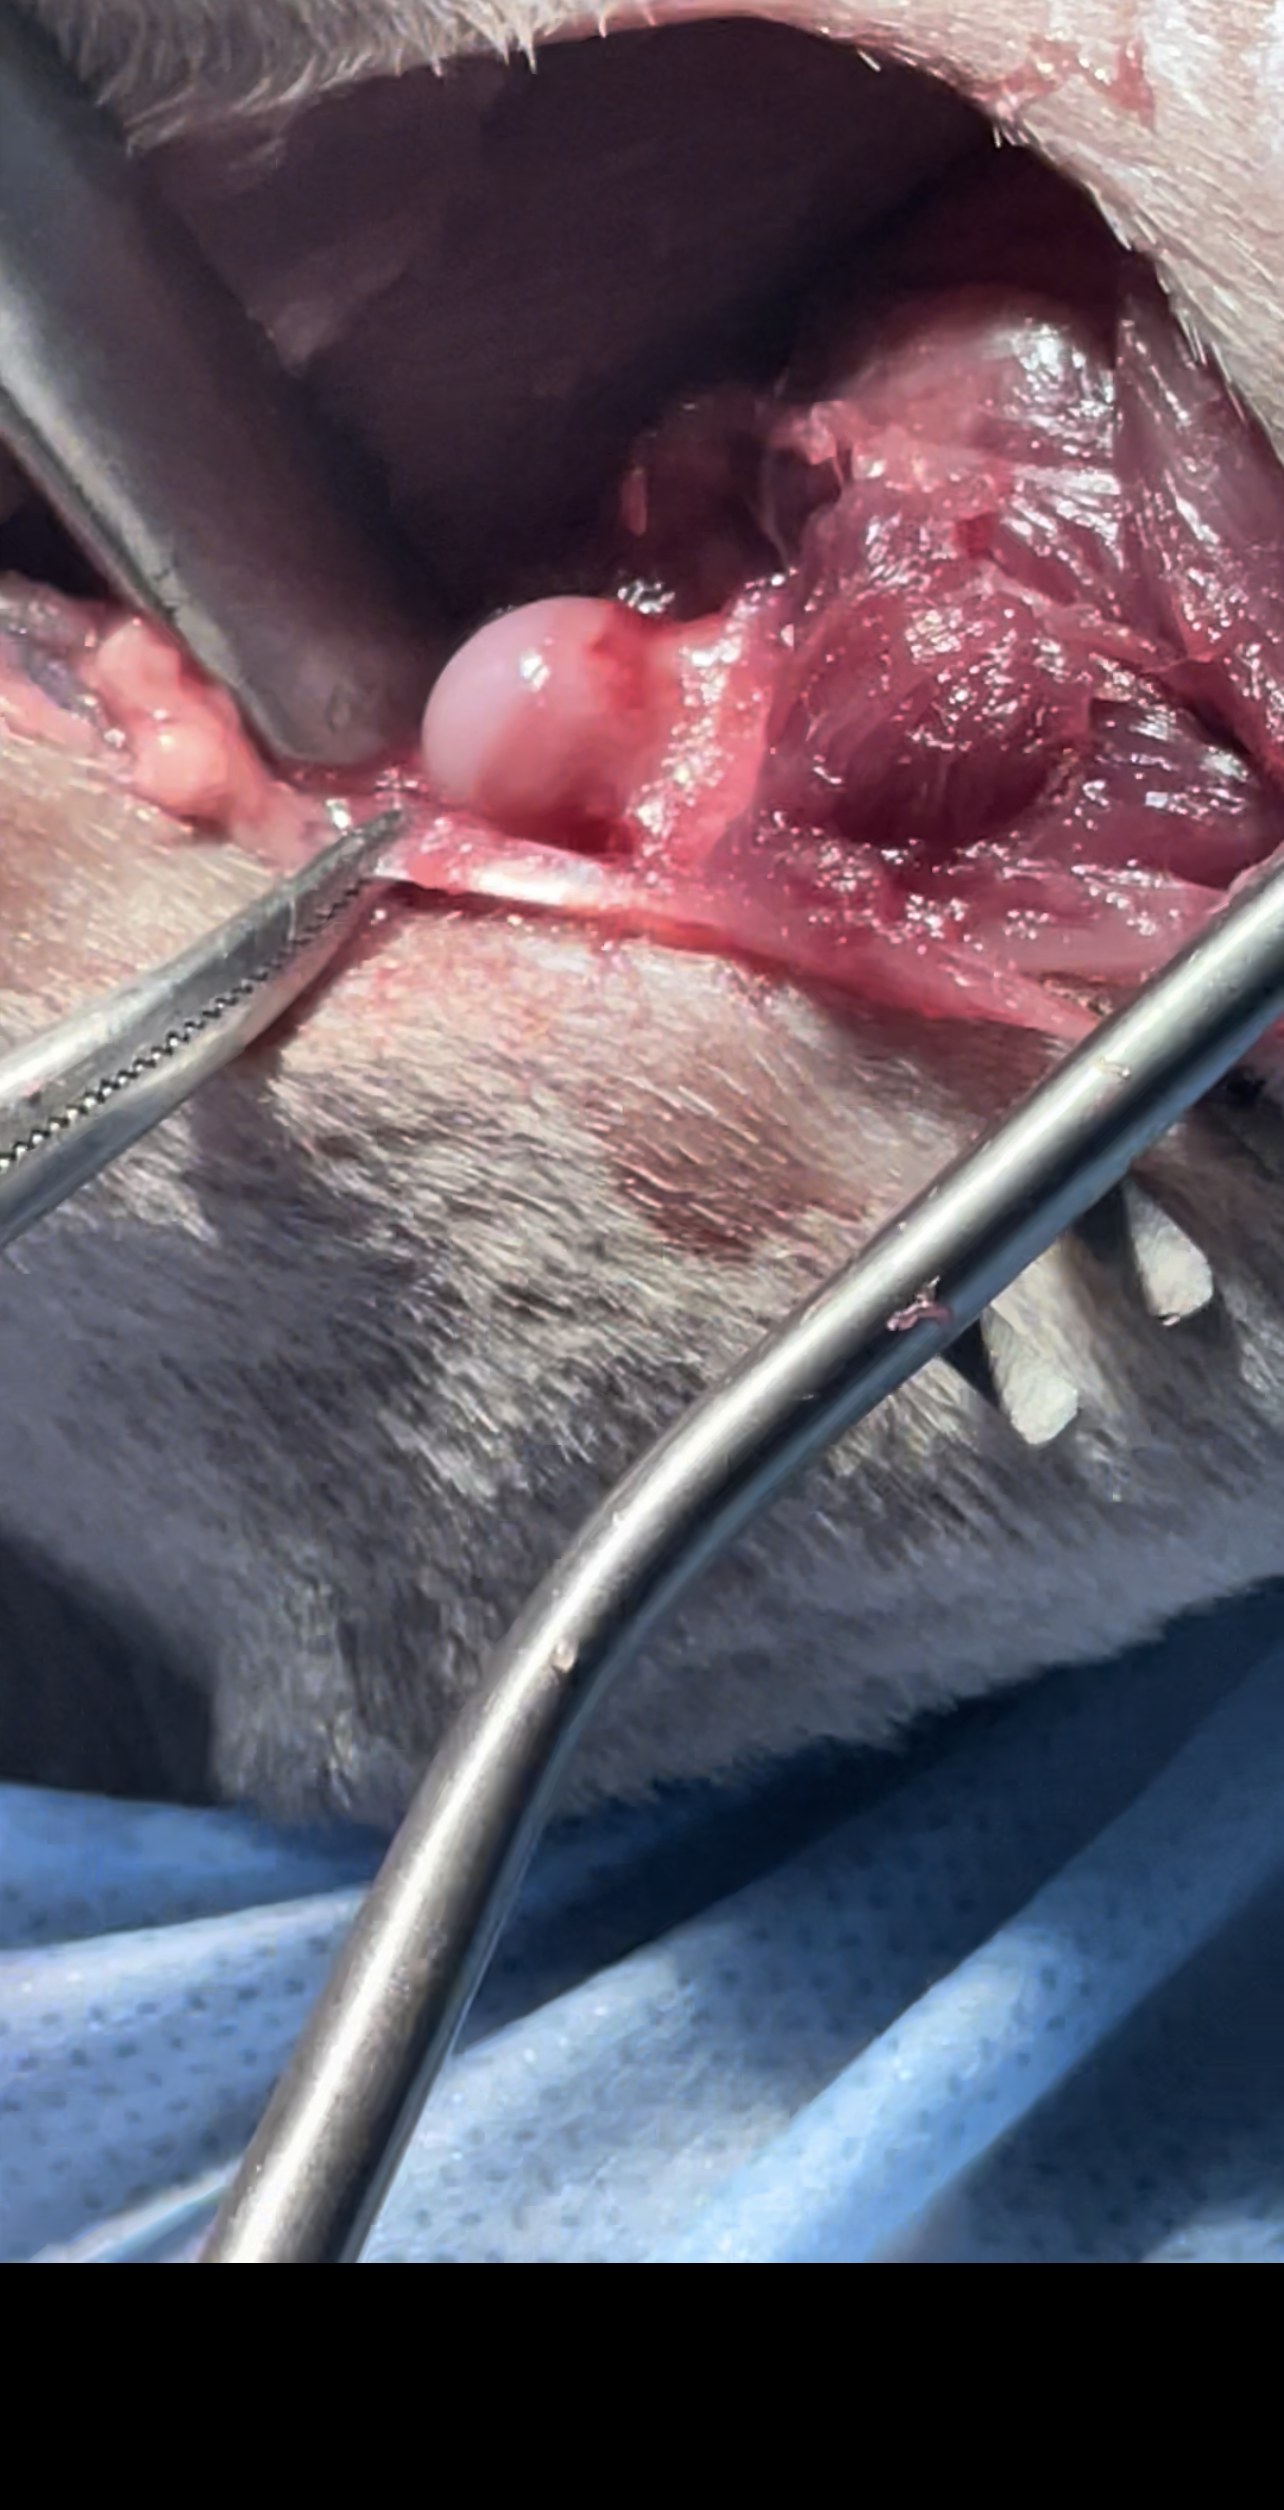

The surgery involves removing the femoral head and neck, thereby eliminating bone-to-bone contact and allowing a fibrous pseudoarthrosis (“false joint”) to form

Surgery

Bilateral FHO was recommended starting with the right most affected limb and the other to be scheduled after 2 months